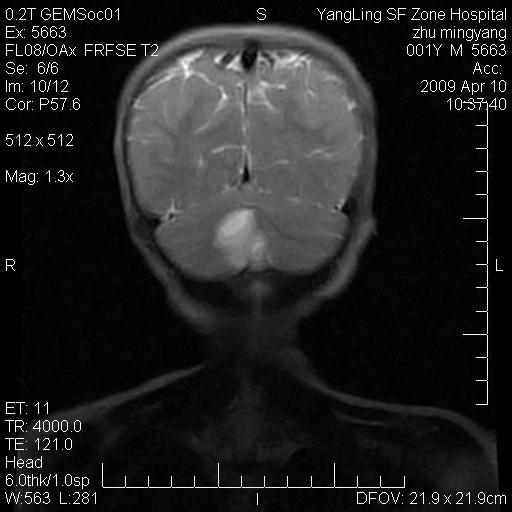

患者:1岁半,两天前外伤收住我院,ct检查小脑占位

考虑星形细胞瘤,建议增强

髓母细胞瘤或血管母细胞瘤,增强后可以鉴别;影像资料见 <。鱼博浪老师的《中枢神经系统ct与mr鉴别诊断》 小脑部肿瘤章节。

髓母细胞瘤或血管母细胞瘤!支持!

支持考虑髓母细胞瘤

考虑----髓母细胞瘤可能性大

考虑髓母细胞瘤或室管膜瘤。

支持髓母细胞瘤。

考虑髓母细胞瘤。

考虑髓母细胞瘤或星形细胞瘤

考虑髓母细胞瘤.

考虑髓母细胞瘤可能性大。

小脑肿瘤.考虑髓母细胞瘤可能.

就病灶部位及临床资料首先考虑髓母.